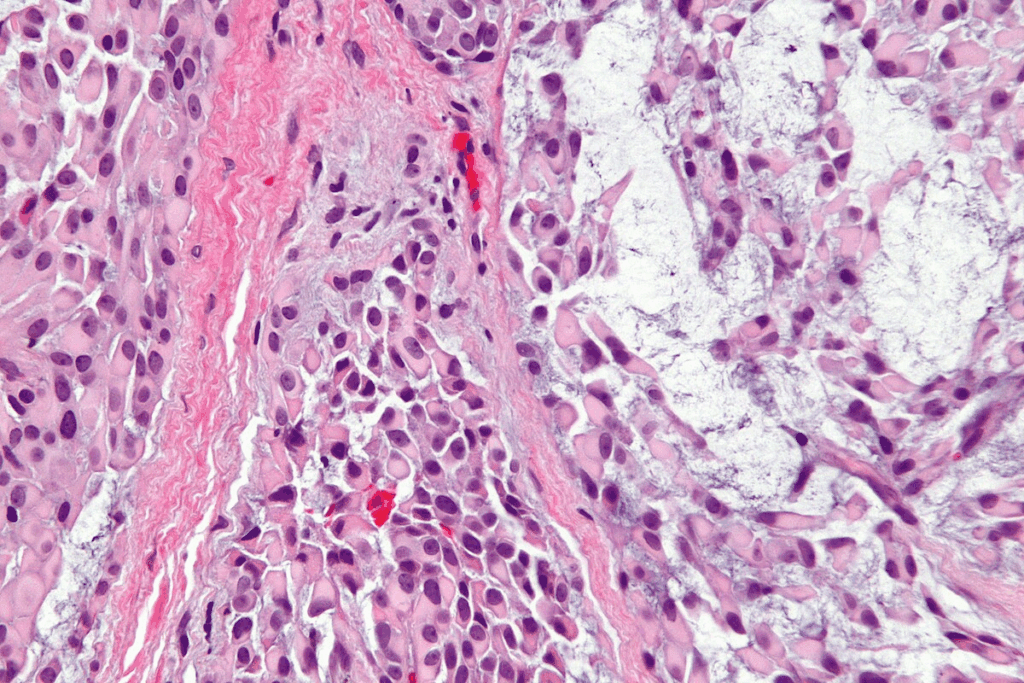

Cellular Structure and Abnormalities

Neoplastic cells look different under a microscope. They can be bigger, smaller, or shaped differently. These changes help doctors spot tumors.

- Anaplasia: Cells lose their normal shape, looking like young cells.

- Pleomorphism: Cells vary in size and shape, showing a loss of normal structure.

- Hyperchromasia: Nuclei are darker because they have too much DNA.

Biopsy and Histopathological Analysis

The final diagnosis often comes from a biopsy and histopathological analysis. A biopsy takes a tissue sample from the suspected tumor. A pathologist then examines it under a microscope.

The histopathological analysis gives important info about:

- Tumor type

- Grade of malignancy

- Presence of genetic mutations